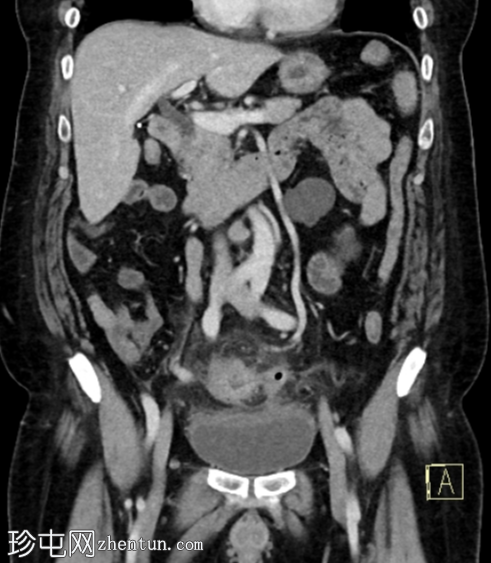

冠状位增强扫描(门静脉期)

先前观察到的乙状结肠壁增厚和结肠周围脂肪间隙模糊进展,并新发现左侧结肠周围小软组织密度影(蜂窝织炎),大小为3.0 x 2.0 cm,可见中央气腔。该蜂窝织炎位于先前观察到的左侧壁缺损附近。

膀胱顶部反应性壁增厚。

未见气腹、腹水或腹腔内脓肿。

病例讨论

该病例表现出复杂性急性乙状结肠憩室炎的典型特征,伴有乙状结肠局部穿孔,提示为1A期复杂性急性憩室炎。患者接受了广谱抗生素保守治疗,1个月后因临床症状加重前来复诊。复查CT显示乙状结肠憩室炎恶化,出现结肠周围小蜂窝织炎,内含少量气腔。但未见弥漫性腹膜炎的征象,如腹水、气腹或弥漫性腹膜/大网膜混浊。之后患者失访。